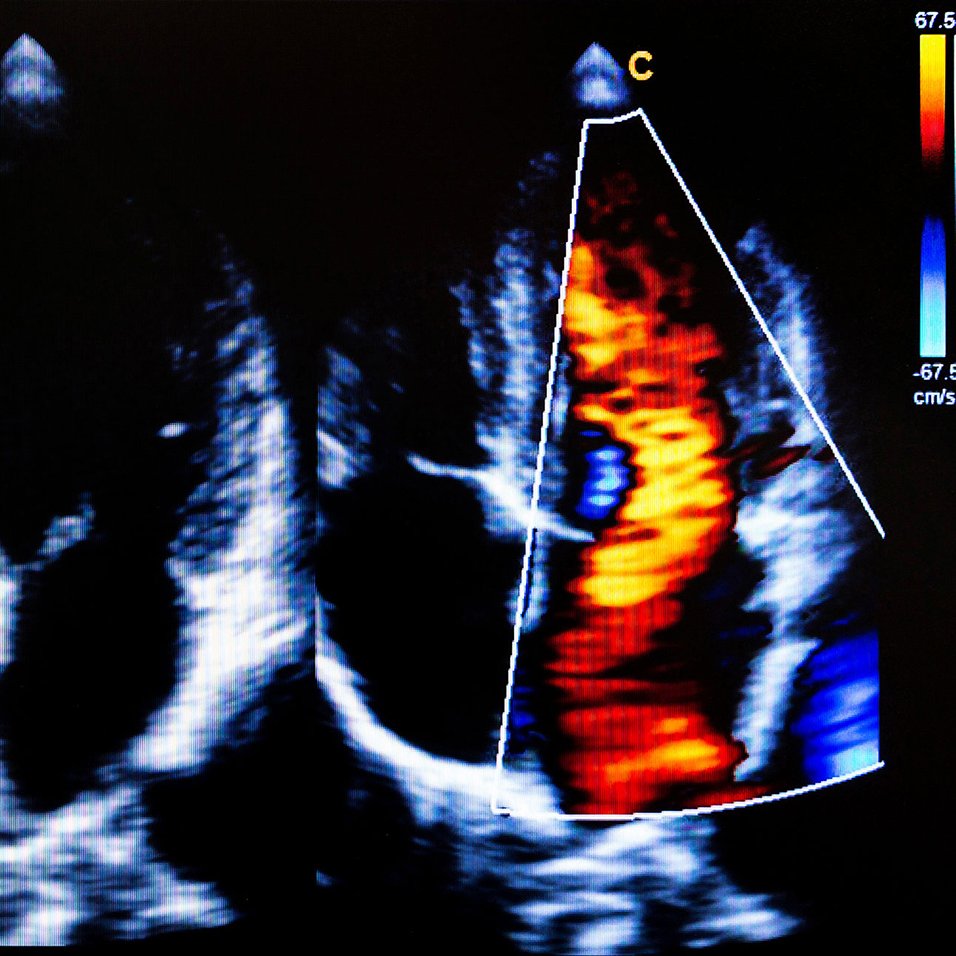

Comment retrouver des contractions cardiaques synchrones ?

Grâce à un pacemaker relié par des sondes au muscle cardiaque, il est possible de rendre au cœur une activité contractile synchronisée...